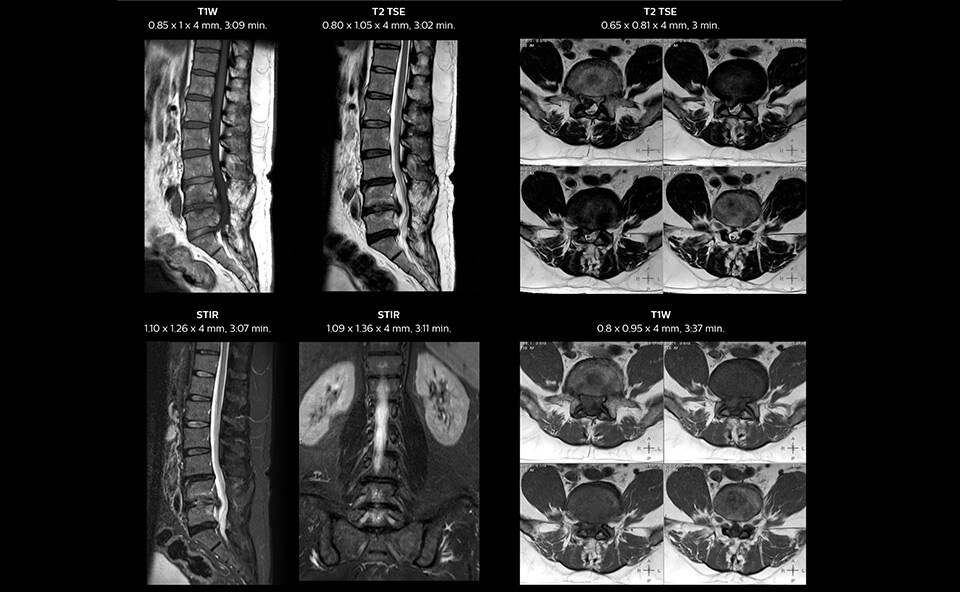

In this patient MRI images show spondylotic degenerative changes in the lumbar spine, in view of the osteophyte, disc desiccations and Sc hmorl’s nodes with lumbarization of S1, post-laminectomy changes at L5-S1 and S1-S2 levels with disc protrusion and extrusion, and diffuse disc bulges from L3-L5 with nerve root compression.